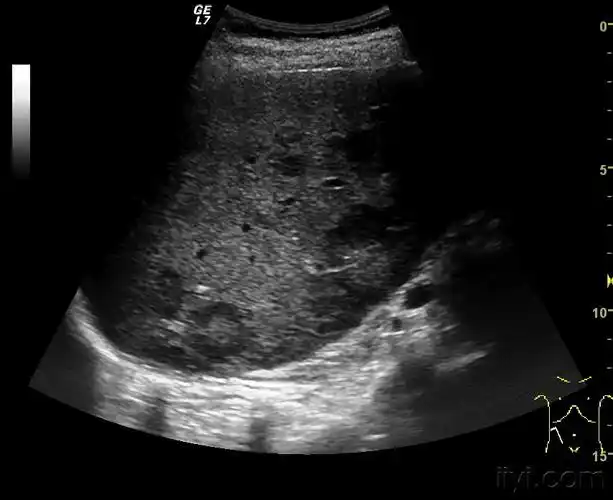

肝内牛眼 - 超声医学讨论版 - 爱爱医医学论坛

牛眼征! - 超声医学讨论版 - 爱爱医医学论坛

牛眼 超声 ct该征象被认为是转移性肝癌典型影像表现,可见于任何转移